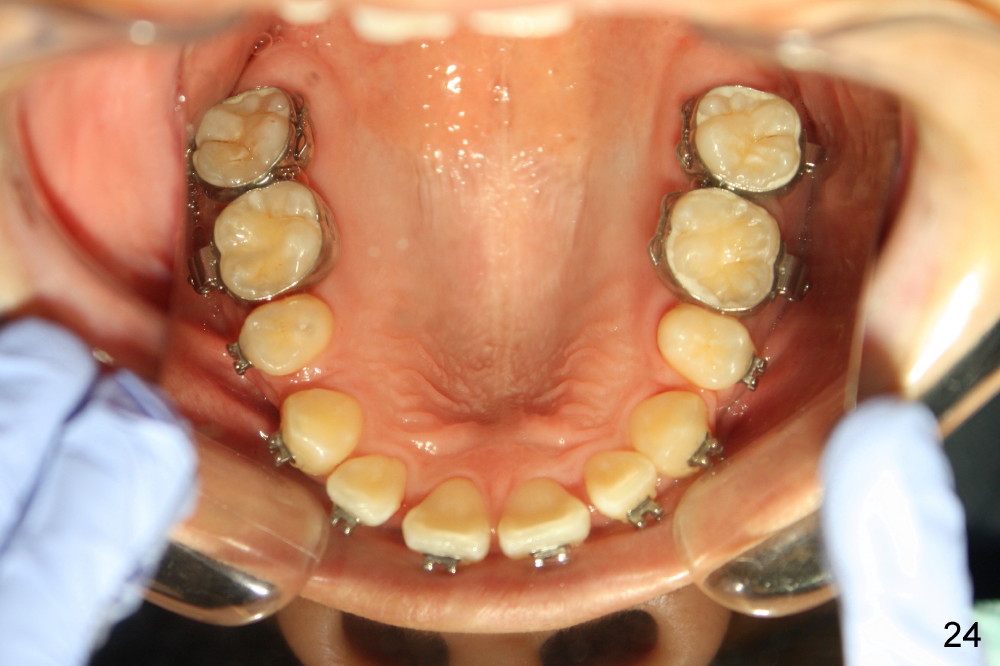

Four and a half months post bracketing (Fig.21-25), what do you find and what should be done next?

Prior to bracketing, the mesiodistal space for #18 is planned to be obtained by moving #20 and then #19 mesially (Fig.31-35, 16x16 ss). The six anterior lower teeth are tied together in a figure 8 fashion. Power chains are placed between the lower canine and the 2nd bicuspids. The upper diastemata are to be closed by power chains between the 1st molars.